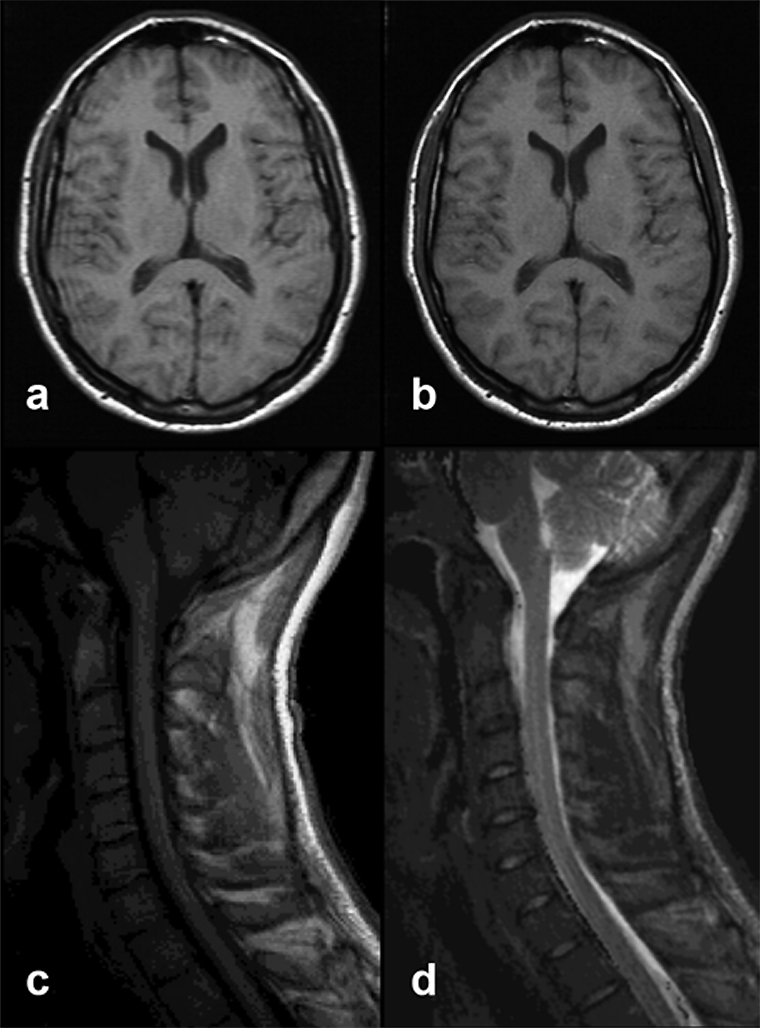

Figura 17-13:

Truncation artifacts.

Top: (a) 60% acquisition with ar­tifacts. (b): 80% acquisition, no artifacts visible.

Bottom: Truncation artifact mimicking sy­ringo-myelia. (c) T1-weighted, (d) T2-weighted im­age.